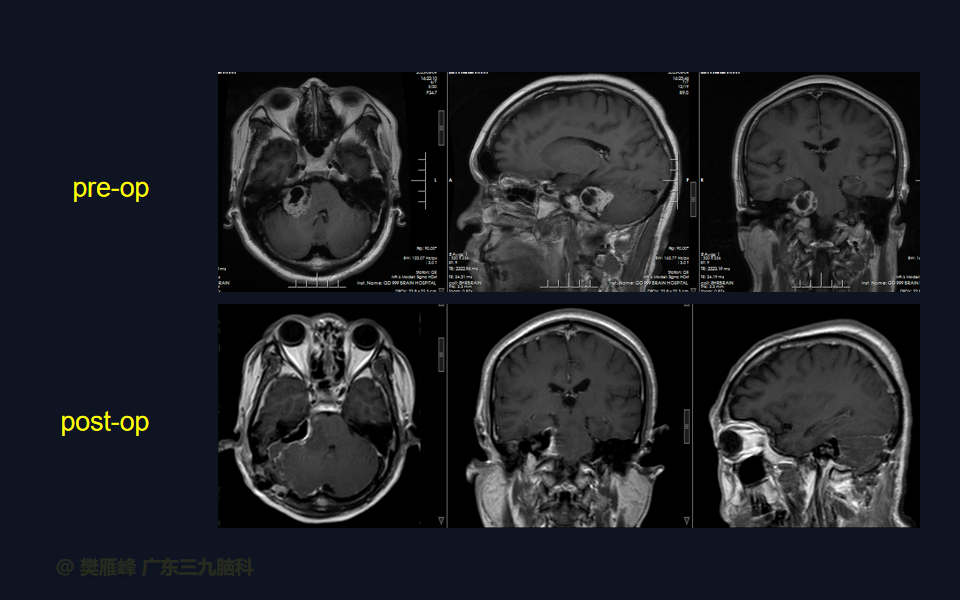

在这个二维手术视频中,展示了一种经枕下乙状窦后入路束膜下分离保留面神经的方法。患者是一名51岁的男性,有1年右耳听力下降伴耳鸣、无步态不平衡病史,术前有右侧轻度面瘫,神经影像学显示右侧桥小脑角区约30×30×29mm的囊实性占位,增强后实性部分及囊壁可见明显强化。他接受了经乙状窦后入路保留面神经的方法,术中肿瘤全切除,面神经被肿瘤挤压成薄膜状覆盖于三叉神经表面。术后面瘫加重,听力未能保留,神经影像学显示肿瘤全部切除。我们展示了安全的颅神经保护和肿瘤切除的细微差别和技术要点,以及手术技术。